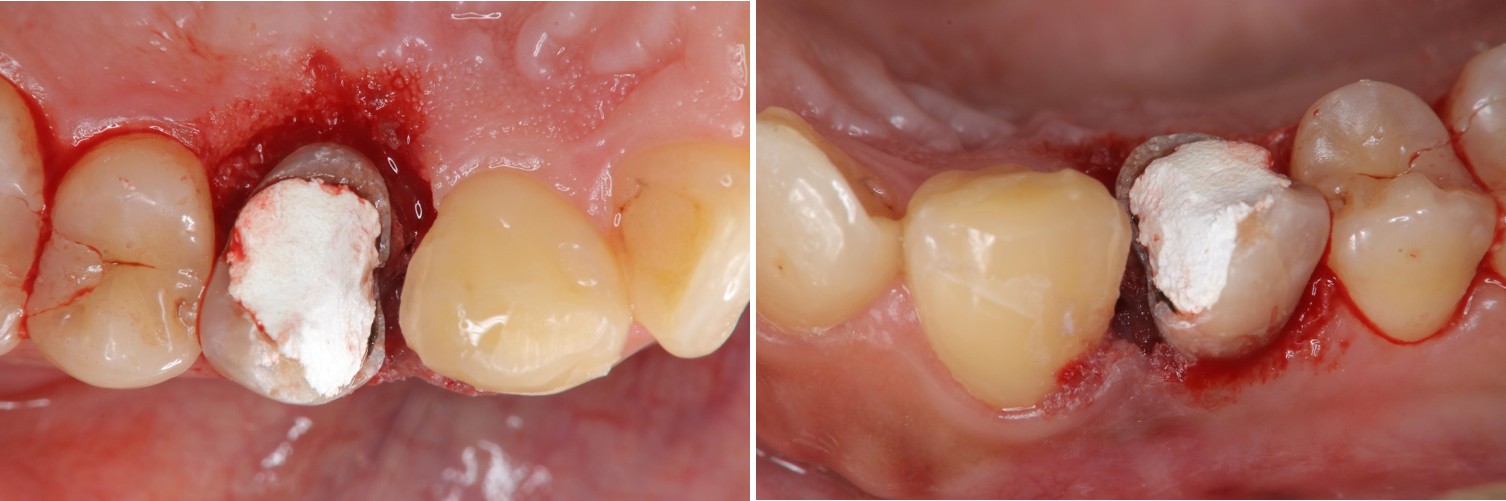

水雷射牙冠增長手術

膺復前評估牙齦、牙齒狀態